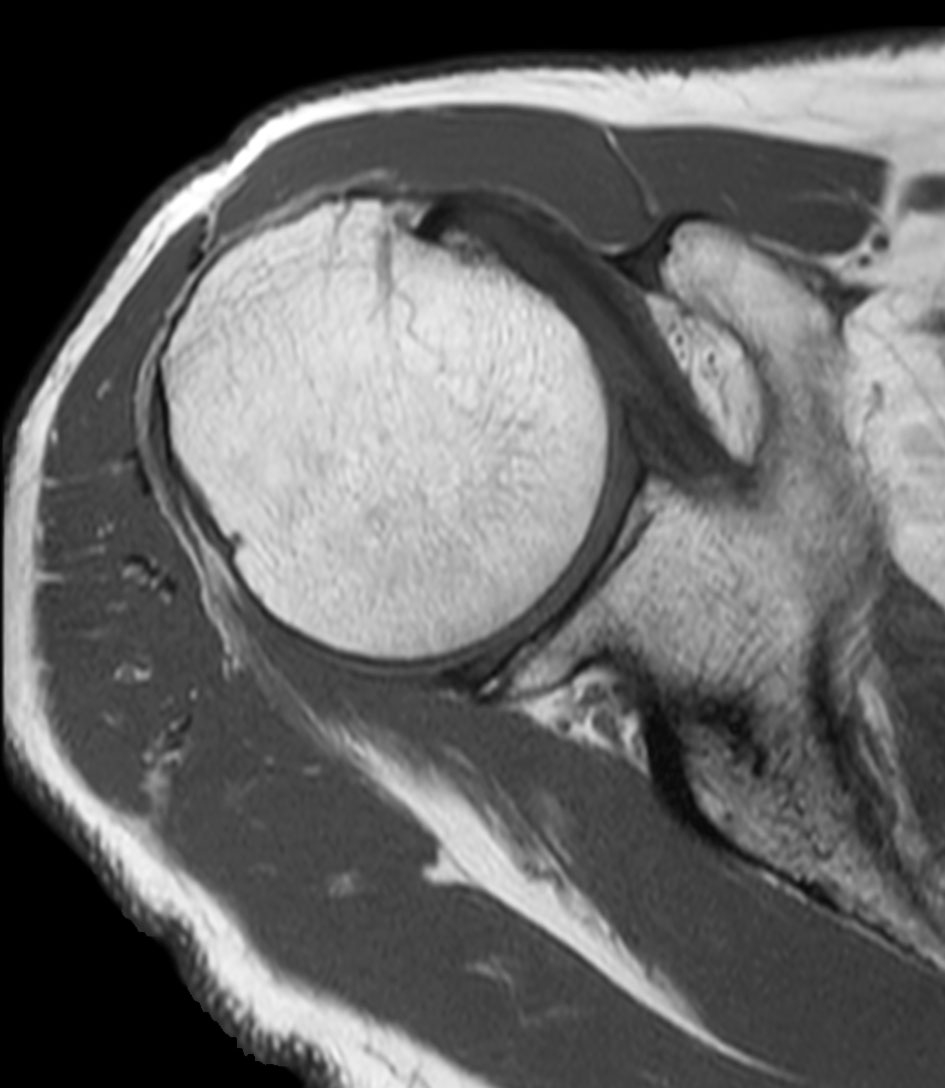

Shoulder imaging using ComforTone